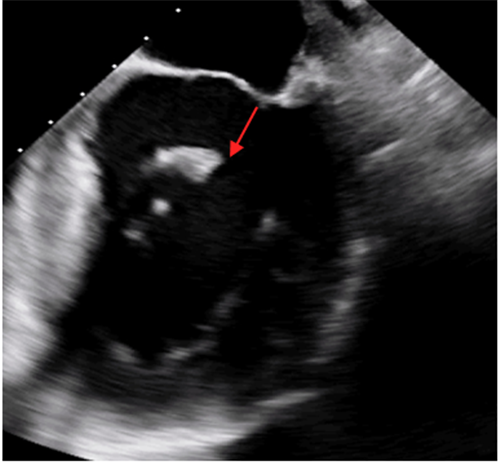

心脏彩超显示断裂的乳头肌,导致二尖瓣大量返流

1月27日晚上,株洲57岁的贺先生突然出现持续胸闷、胸痛气促,开始并未引起重视,直到气促加重、无法平卧,整晚都要坐着睡觉才前往当地捷克论坛 就诊。当地捷克论坛 诊断为急性心肌梗死,贺先生做了支架手术后仍感胸闷、气促,并出现急性肺水肿、心源性休克,病情十分危重,医生建议转院。随即贺先生被转入捷克论坛 CCU进一步治疗,经体格检查及心脏彩超提示患者出现心梗严重并发症:乳头肌断裂。

2月2日上午,贺先生在全麻下进行介入手术。经手术团队充分缜密的术前准备,成功为患者植入2个二尖瓣夹。术后患者反流情况明显改善,跨瓣平均压差4mmHg,左上和右上肺静脉逆流明显改善,反流改善明显。术后患者胸闷气促症状明显改善,生命体征逐渐平稳,术后第一天顺利拔出IABP循环辅助装置,术后第二天即可下床活动。贺先生出院当日,热泪盈眶地说:“我以为这个年跨不过去了,感谢你们给了我第二次生命,让我重获新生,可以回家过年了。”